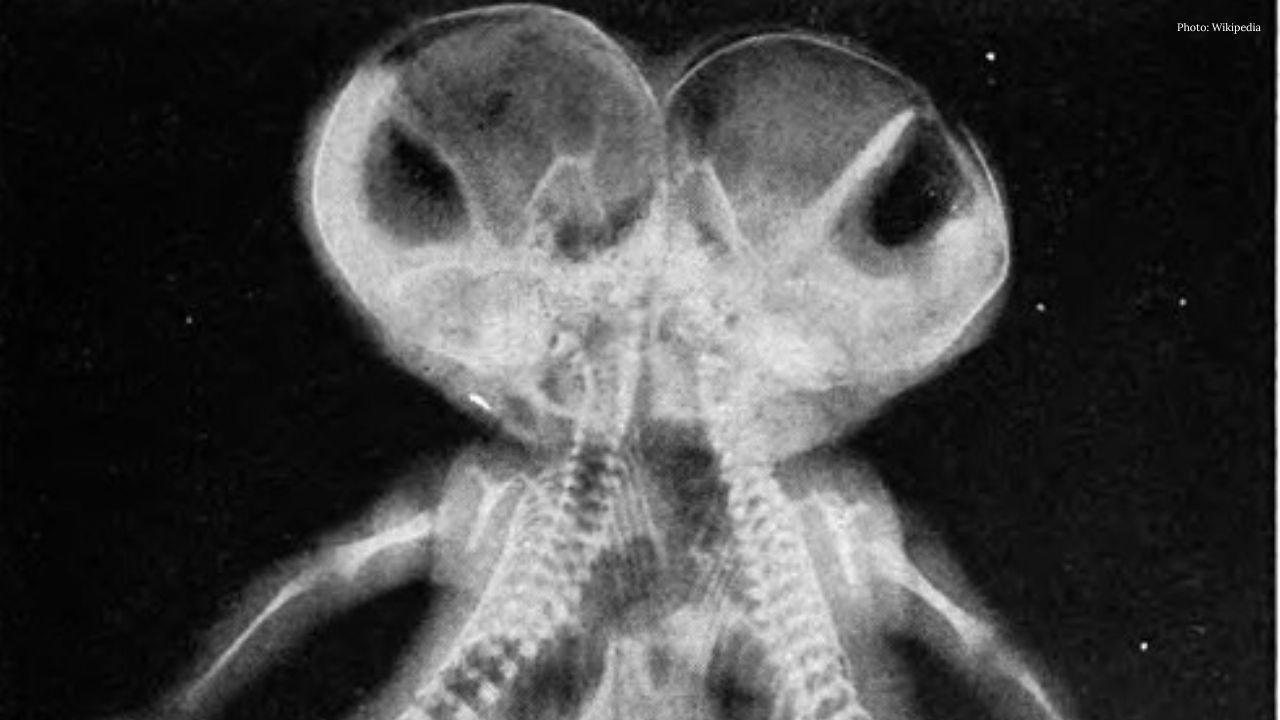

Riyadh, Saudi Arabia — Twin brothers Sufyan and Yusuf, who are conjoined at birth and originally from Pakistan, arrived in Saudi Arabia on Monday for medical evaluation ahead of a possible separation surgery.

At the hospital, the twins’ condition will be assessed by a specialist medical team led by Dr. Abdullah Al‑Rabeeah, head of the country’s Saudi Conjoined Twins Program. Saudi officials say the Kingdom’s accumulated expertise in separating conjoined twins has made it a leading global destination for such procedures.